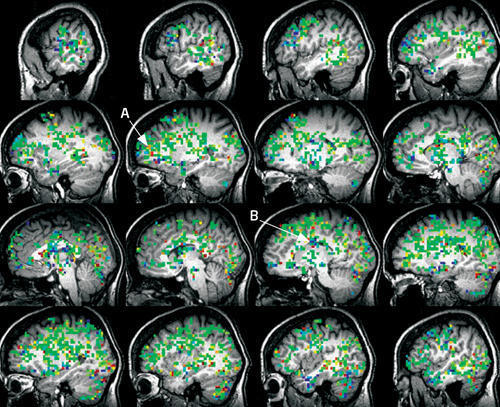

"Orgasm is a special case of consciousness," says Barry Komisaruk at Rutgers University in Newark, New Jersey. "If we can look at different ways of inducing orgasm, we may better understand how we can use top-down processing to control what we physically feel."

People who suffer from chronic pain conditions can be coached to relieve some of their symptoms through such top-down techniques, says Kenneth Casey at the University of Michigan in Ann Arbor. That is, they can use high-level mental processes to modulate what they feel physically. "The placebo effect is an easy example of practical top-down control. You believe you are taking a pill that will help and somehow it does," he says. "In my experience, simply telling a patient that the pain they are experiencing is not harmful has an analgesic effect."

Researchers from Stanford University in California recently showed that individuals were able to control pain by watching real-time activity of a brain area called the rostral anterior cingulate cortex (ACC) and then mentally adjusting it. The ACC is also activated in orgasm.

A better understanding of what these brain areas are doing in situations of pain and pleasure, Komisaruk argues, may open the door for improved top-down techniques to modulate both.

А что за исследование? Томограмма? МРТ?